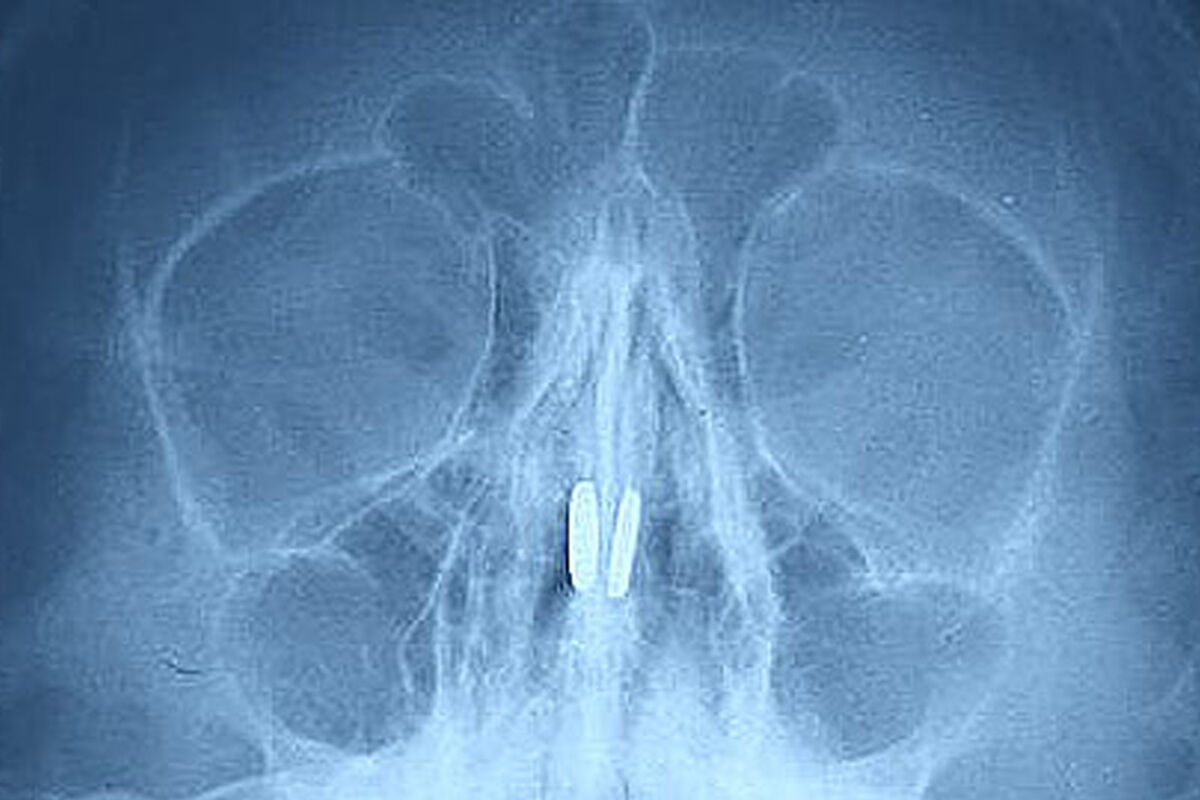

В Нижегородской области врачи извлекли из носа ребенка магнитные шарики, которые притянулись друг к другу. Об этом в Telegram-канале сообщил главный редактор местного издания «Стационар-Пресс» Алексей Никонов.

Маленький пациент был доставлен в медицинское учреждение с жалобами на боль в носу и проблемы с дыханием. В ходе обследования в носовых пазухах были обнаружены магниты от игрушки, которые притянулись друг к другу через носовую перегородку.

Инородные тела извлекли специальным крючком, серьезных повреждений мальчик не получил.